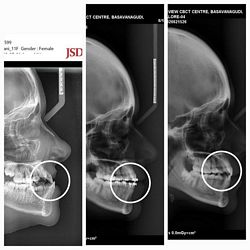

Pre-treatment : Lateral Ceph

Pre, Mid & Post-treatment : Lateral Ceph